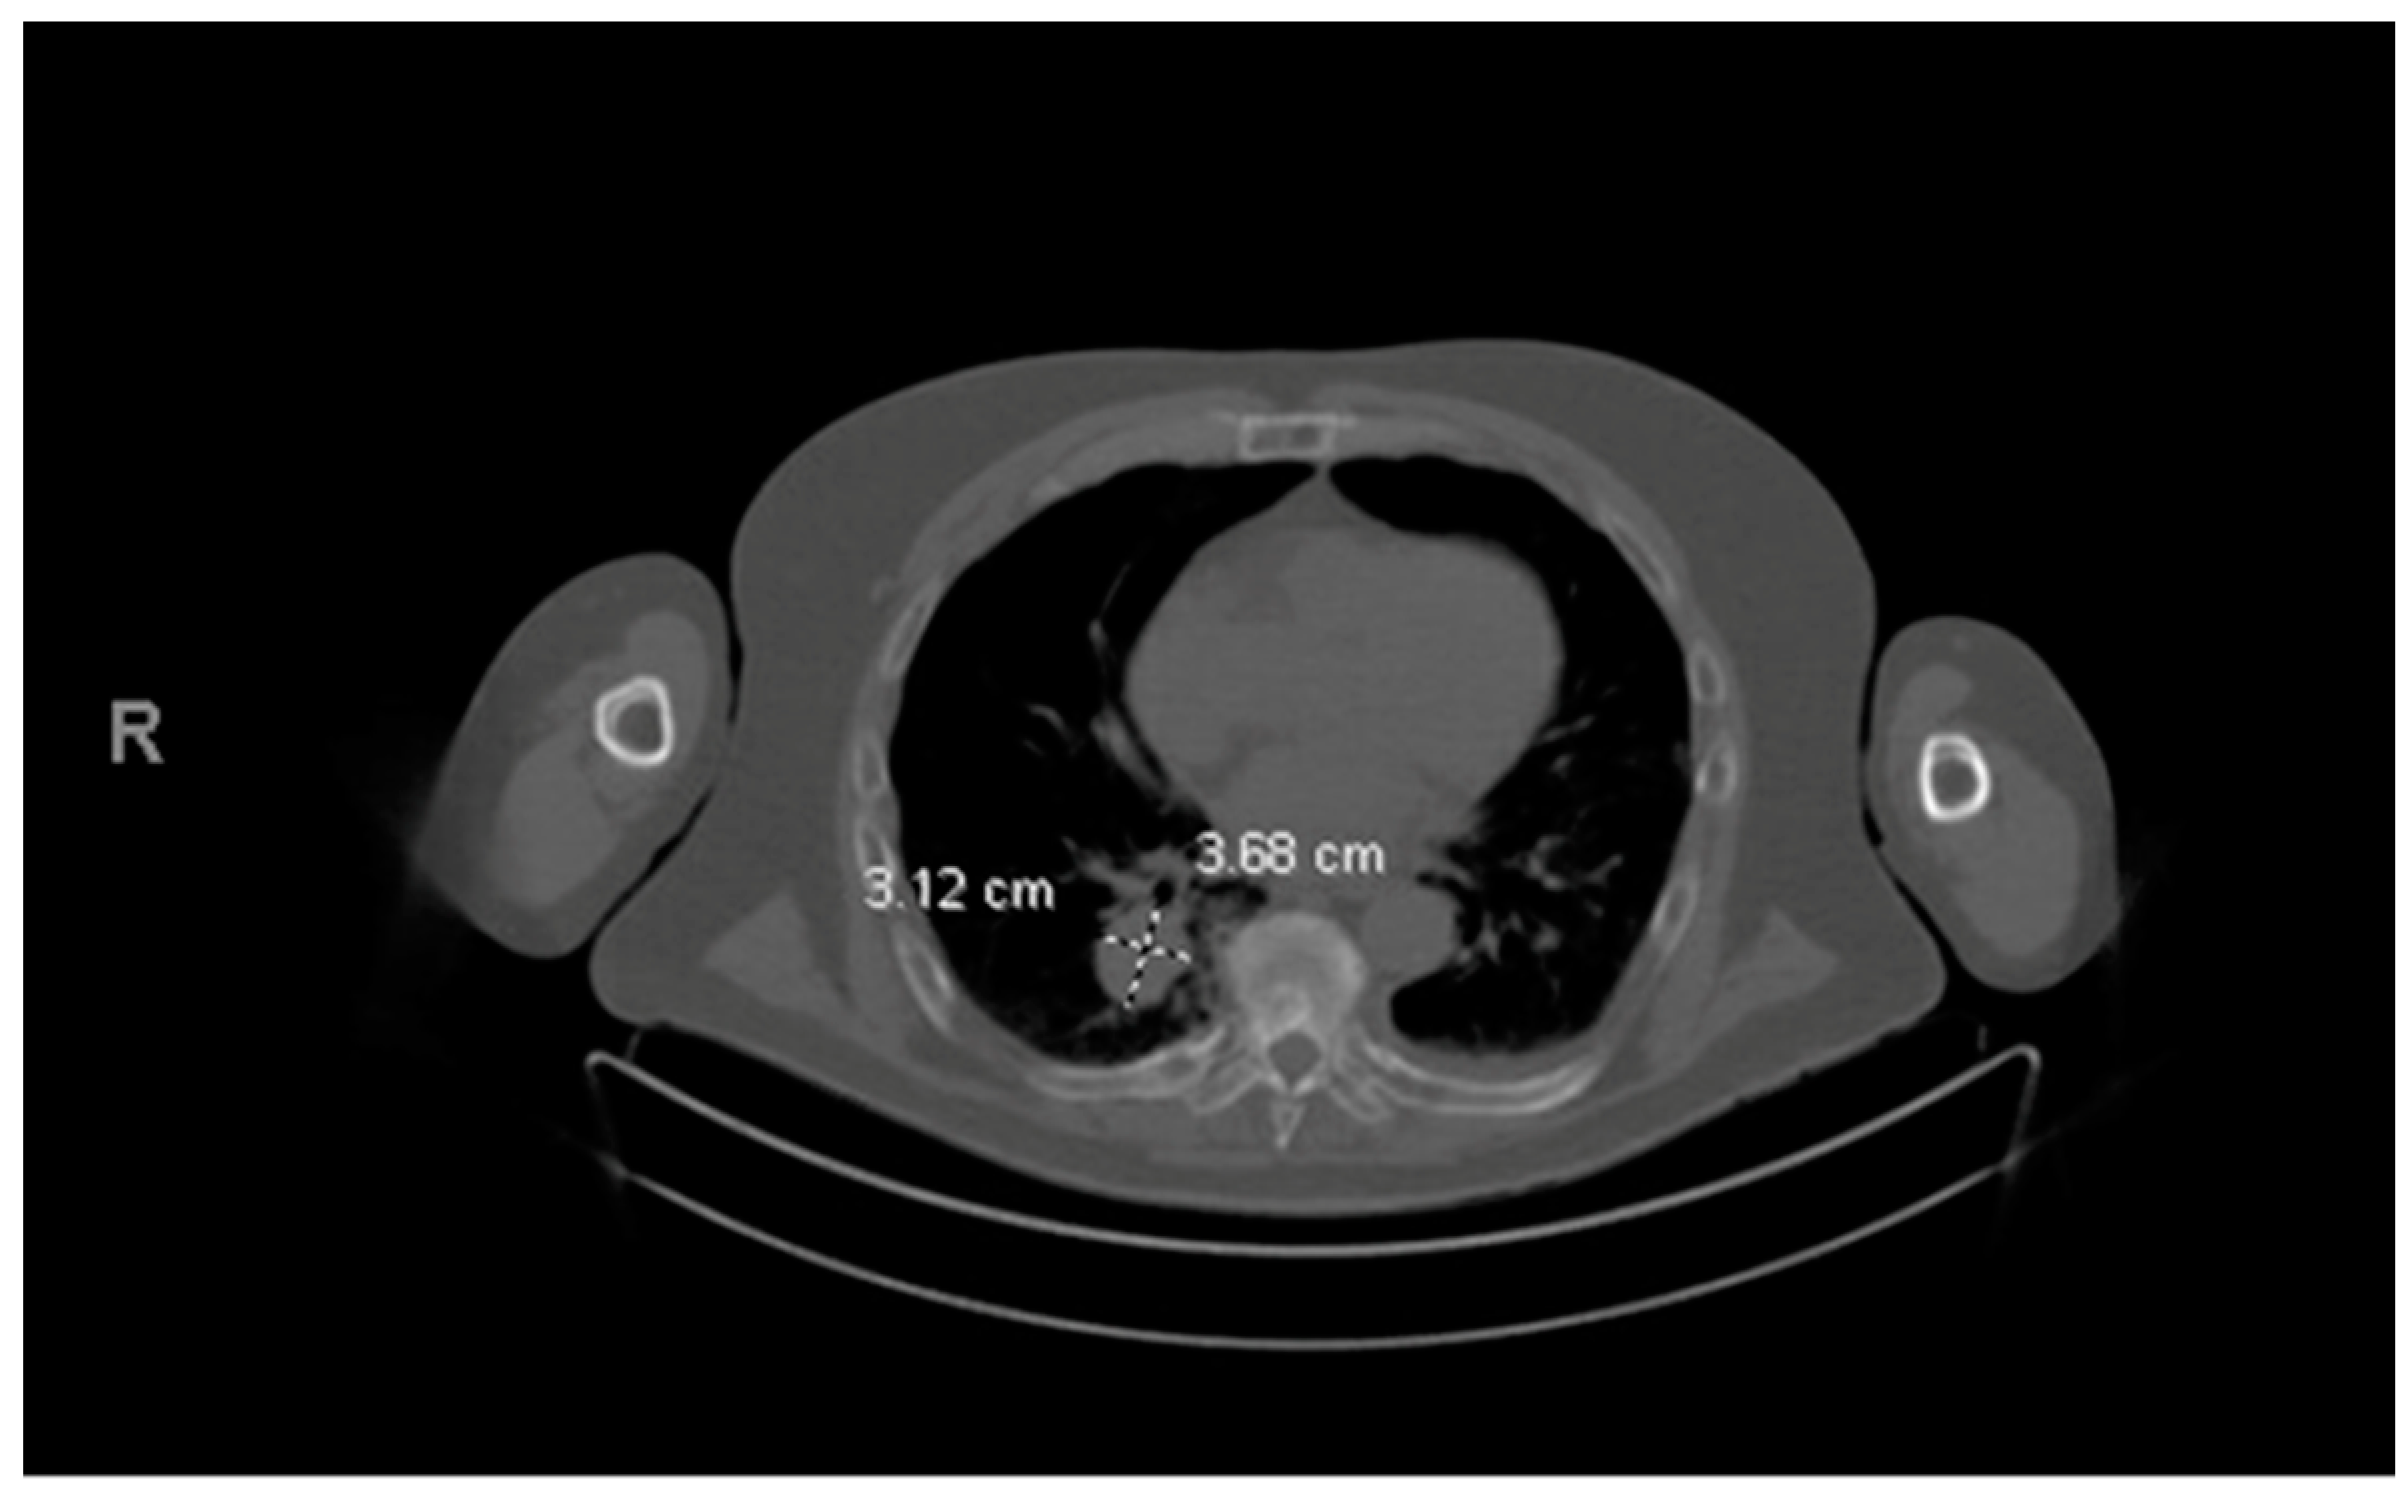

His MM course began with an initial diagnosis of MM one year before admission. At that time, he presented with back pain and was found to have multiple bony lesions. Bone marrow biopsy revealed 52% clonal plasma cells and femur biopsy confirmed bone plasmacytoma finalizing his diagnosis of multiple myeloma. FISH showed t (11:14) rearrangement indicating standard risk cytogenetics. The patient initially responded well to treatment, but unfortunately his disease progressed quickly so he was unable to undergo ASCT. Prior to his hospital stay, a year following the initial diagnosis, a routine positron emission tomography (PET) scan revealed a right lower lobe pulmonary mass, later proven to be a pulmonary (extramedullary) plasmacytoma (Figure 5 and Figure 6). A detailed course of the disease is provided in Figure 7.

Figure 5. Right lower lobe mass later confirmed to be plasmacytoma by wedge resection.